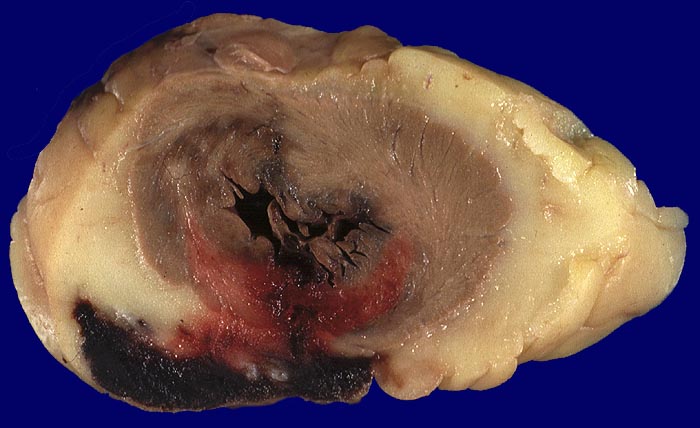

Makroskopie

Pathologischer Befund